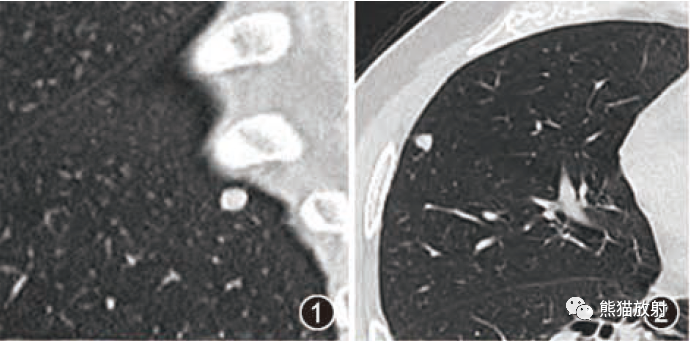

IVP (2005): Preliminary scout images demonstrate a cluster of at least three radiopaque stones in the upper pole of the right kidney; the largest two stones in this cluster each measure 6 mm in diameter. In addition, there are probable clusters of smaller stones in the interpolar right kidney and right lower pole. Following the uneventful intravenous administration of 150 mL of nonionic contrast material, prompt nephrograms develop, which show the kidneys to be normal in size, shape, appearance, and internal architecture. There is diffuse bilateral tubular ectasia. Contrast is excreted promptly into otherwise normal-appearing pyelocalyceal systems. The calculi are no longer seen and likey reside in dilated tubules. The ureters are normal in course, caliber, and appearance. The urinary bladder has a mildly trabeculated appearance. There are two small urinary bladder diverticula: one of the bladder dome and one arising from the left lateral bladder wall. No filling defects are seen.

IVP:预扫定位像可见右肾上极至少3个阳性结石,簇状分布,最大的两个直径约6mm。另右肾中部及下极可见成簇的小结石。静脉注射非离子型对比剂150ml,立即摄片,可见肾脏大小、形态、表现及内部结构正常,可见弥漫性双侧肾小管扩张,造影剂进入正常的肾盂肾盏系统。钙化并未显示,可能在扩张的肾小管内。输尿管走行、直径及表现正常,膀胱轻度小梁形成,可见两个小膀胱憩室,一个位于膀胱顶壁,一个位于左侧壁;未见充盈缺损。